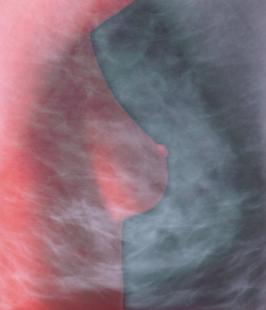

Crédit photo : MEHAU KULYK/SPL/PHANIE